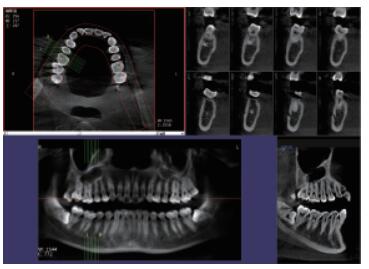

普愛口腔CT設備圖像質(zhì)量高產(chǎn)品說明:

口腔CT能反映各部位的情況,發(fā)現(xiàn)普通牙片、全景片不能發(fā)現(xiàn)的問題,特別是一些更細微的病變,是口腔醫(yī)院中常用到的一款設備。為了讓患者放松,保證掃描期間處于正確位置,提高拍片成功率,提前做好充分準備工作是口腔拍片過程中的一個重要步驟,是有助于執(zhí)行正確的掃描并獲得高質(zhì)量的圖像。下面小編給大家介紹下口腔CT拍片前準備工作和擺位的注意事項。

運用口腔CT進行檢查可以大大提高口腔科臨床水平。以普愛醫(yī)療口腔CT為例,(它)可用于口腔種植、正畸、牙體牙髓、牙周、顳下頜關(guān)節(jié)、頜面外科及其他診斷需求,它有掃描速度快、成像速度快、操作軟件專業(yè)性強等優(yōu)點,它可以輔助各種臨床診斷與治療??谇籆T產(chǎn)品特點:

CMOS成像質(zhì)量優(yōu)

采用高端平板探測器,分辨率高、圖像質(zhì)量優(yōu)。

三維重建任意斷層

專有三維重建算法,可提供任意位置高清斷層影像。

高清口腔全景影像

通過三維容積影像,提取高清口腔全景影像。

多平面組合重建

可同時觀察軸向面、冠狀面和矢狀面圖像,方便臨床診斷。